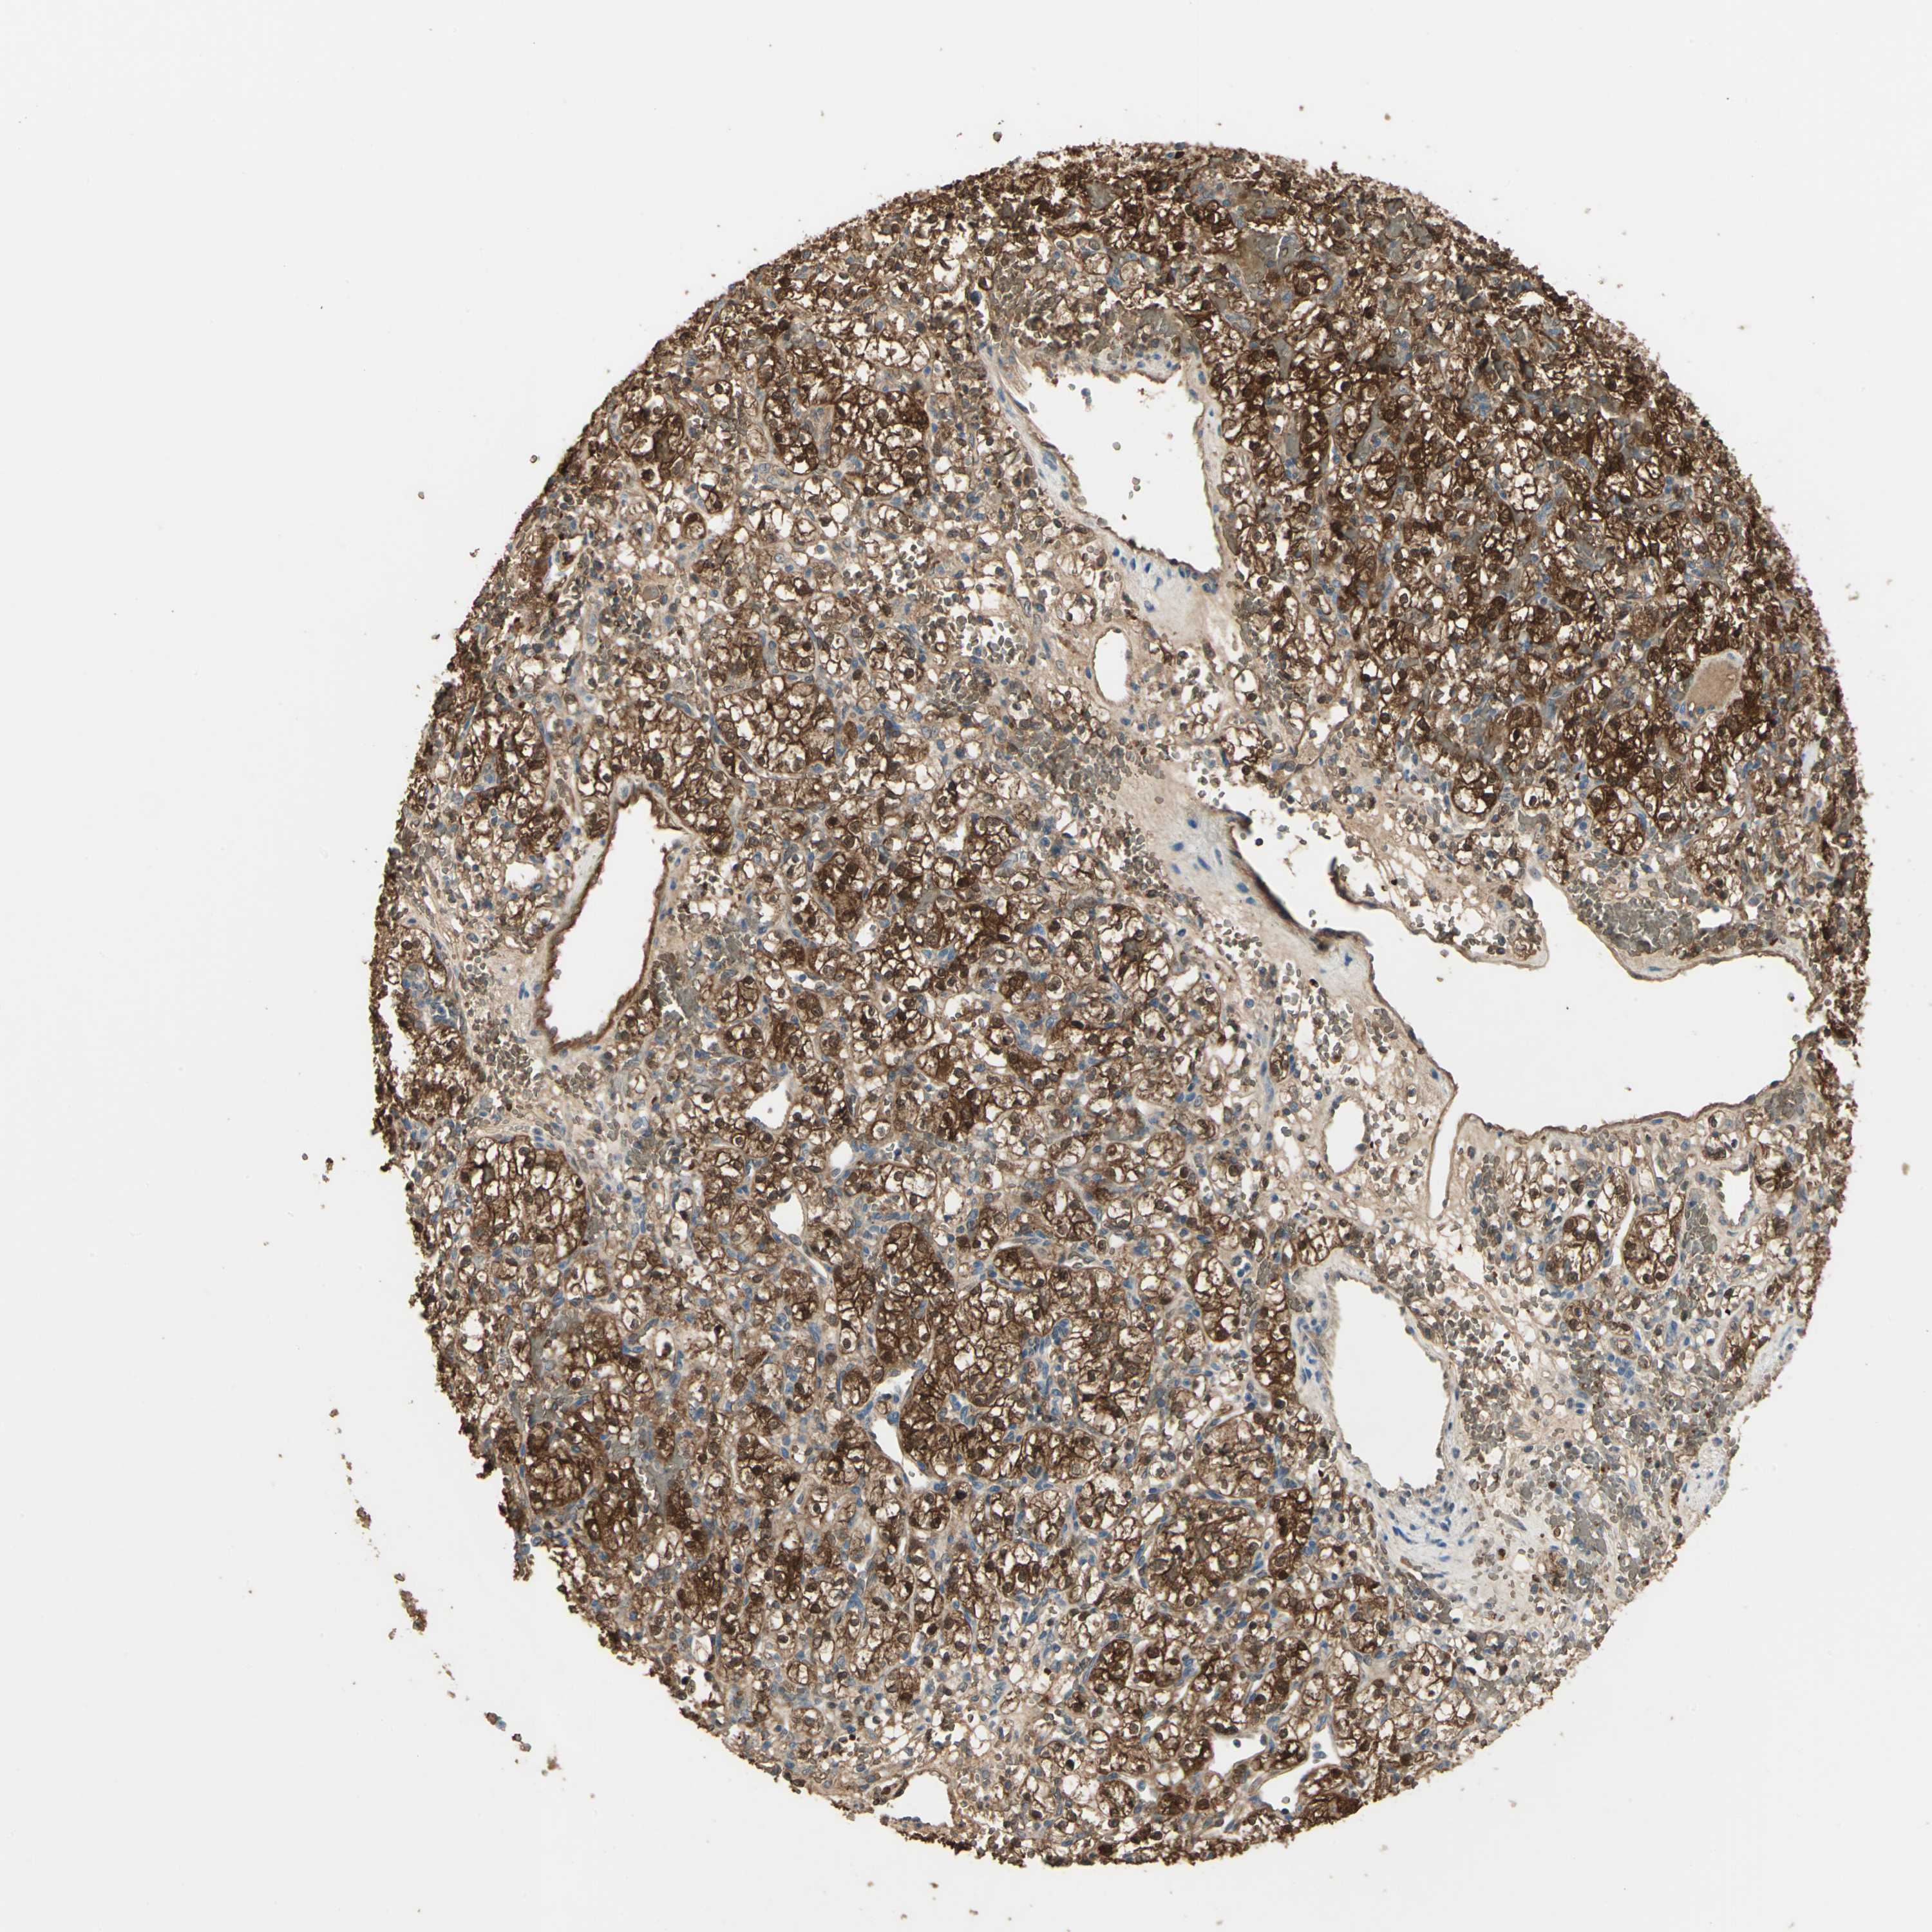

CANCER RENAL CANCER Show tissue menu

KICH TCGA KIRC TCGA KIRC VALIDATION KIRP TCGA PROTEIN RCC CPTAC PROTEIN EXPRESSION

Renal cancer

Kidney renal papillary cell carcinoma

DDAH1 is not prognostic in Kidney Renal Papillary Cell Carcinoma (TCGA)